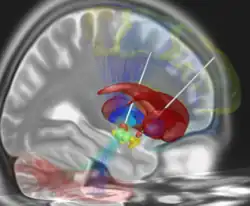

La stimulation cérébrale profonde est un traitement médical invasif (neurochirurgical) consistant à implanter chirurgicalement dans le cerveau des électrodes, connectées à un boîtier mis en place sous la peau et qui délivre un courant électrique de faible intensité dans certaines structures spécifiques situées en profondeur de cet organe comme le thalamus ou certains noyaux des ganglions de la base, comme le noyau sous-thalamique ou le globus pallidus. Les sites stimulés varient selon l'indication : Ce traitement peut en effet être utilisé pour traiter des maladies neurologiques, telles que la maladie de Parkinson, les tremblements ou les dystonies, mais aussi plus rarement des troubles psychiques résistants aux autres formes de traitements, tels que des formes sévères de TOC ou de dépression.

La cible peut être le noyau sous-thalamique ou le globus pallidus, les deux sites étant équivalents du point de vue de l'efficacité[8]. Elle peut être unilatérale ou bilatérale en cas de résultats insuffisants[9].

Quelques essais ont été faits lors de dépressions graves et résistantes[10] avec des résultats favorables[11], initiés par la neurologue américaine Helen S. Mayberg[12]. Dans ce cas, la stimulation a pour cible l'aire de Brodmann 25[13], située dans le cortex cingulaire antérieur.

Des résultats prometteurs ont été également obtenus dans le cas des troubles obsessionnels compulsifs[14], avec pour cibles possibles le noyau sous-thalamique[15] ou des zones striatales telles que la partie ventrale du bras antérieur capsule interne[16] ou encore le noyau accumbens[17], voire une combinaison de cibles[18].